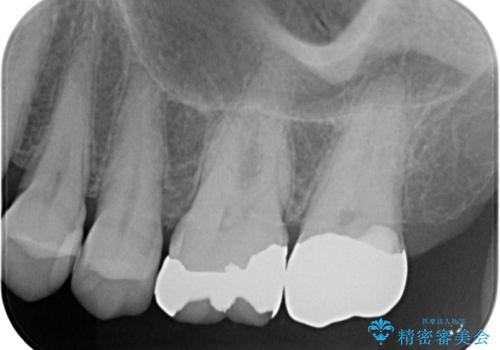

- 上の奥歯を放置してしまったとのことで来院された患者様です。

虫歯が大きいのでクラウンによる治療が必要となりますが、咬む力がとても強いために、歯と同じ堅さであるPGAクラウン(白金加金合金クラウン)をお勧めしました。

上の奥歯であることから、審美性よりも機能性を優先され、ゴールドクラウンを選択されました。

装着後の違和感など一切なく、見た目もほとんど気にならないとのことで、患者様には大変満足していただけました。